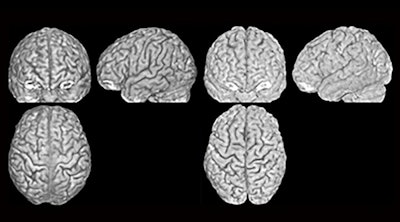

Three MRI scans (front, side, and above) of two different brains (left and right) that belong to twins. The furrows and ridges differ between the two people. Image courtesy of Lutz Jäncke, PhD, University of Zurich.For the study, Jäncke and colleagues imaged brains of 191 healthy older people using MRI three times over a period of two years. More than 450 brain anatomical features were assessed, including general ones such as total volume of the brain, thickness of the cortex, and volumes of grey and white matter (Scientific Reports, April 4, 2018).